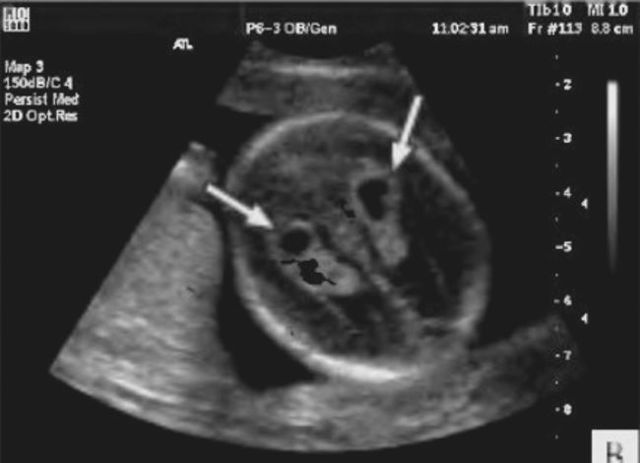

Сосудистые сплетения у плода образуются на сроке 18-19 недель. Именно в этот период, при проведении УЗИ могут быть обнаружены первые признаки кист, которые выглядят, как эхонегативные образования. Чаще всего в срок от 20 до 24 недель, когда идет активное формирование головного мозга, размер кисты уменьшается, и она полностью исчезает.

Образование подобного полостного сплетения, расположенного в правом желудочке мозга, является односторонним. Если у ребенка есть генетические отклонения в структуре мозга, там возможны аномальные изменения. Их легко увидеть во время ультразвукового исследования.При расположении кисты в боковом сплетении наблюдается пониженное ХГЧ, что указывает на врожденную аномальную патологию.

Встречаются также билатеральные кистозные образования сплетений сосудов в мозговых тканях, которые являются двусторонними поражениями. Структура тканей и сосудов мозга не нарушается, но при этом киста затрагивает сплетения сосудов одного бокового желудочка или обоих.